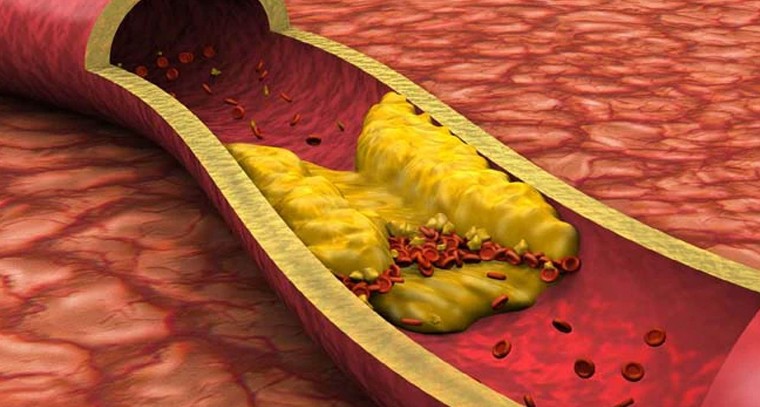

బాడీలోని కొలెస్ట్రాల్ మొత్తాన్ని కరిగించే గింజలు

Publish : Tue, Jun 24, 2025, 11:55 PM

గుండె ధమనుల్లో కాల్షియం పేరుకుపోతే.. పరిణామాలు, పరిష్కారాలు..!

Publish : Sun, Jun 22, 2025, 04:16 PM